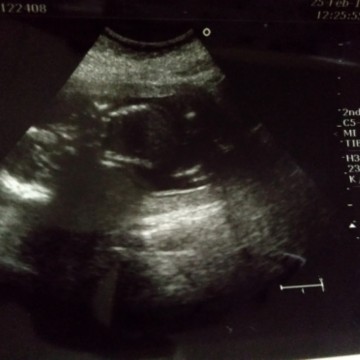

อยากรู้เพศ

อยากรู้ค่ะว่าเพศหญิงหรือชายพอดีตอนไปซาวคุณหมอไม่ใด้บอก

หมอไม่ได้บอกอาจนะเป็นเพราะยังดูไม่ชัดหรือเปล่าคะว่าเป็นเพศอะไรเลยยังไม่ได้บอกค่ะ